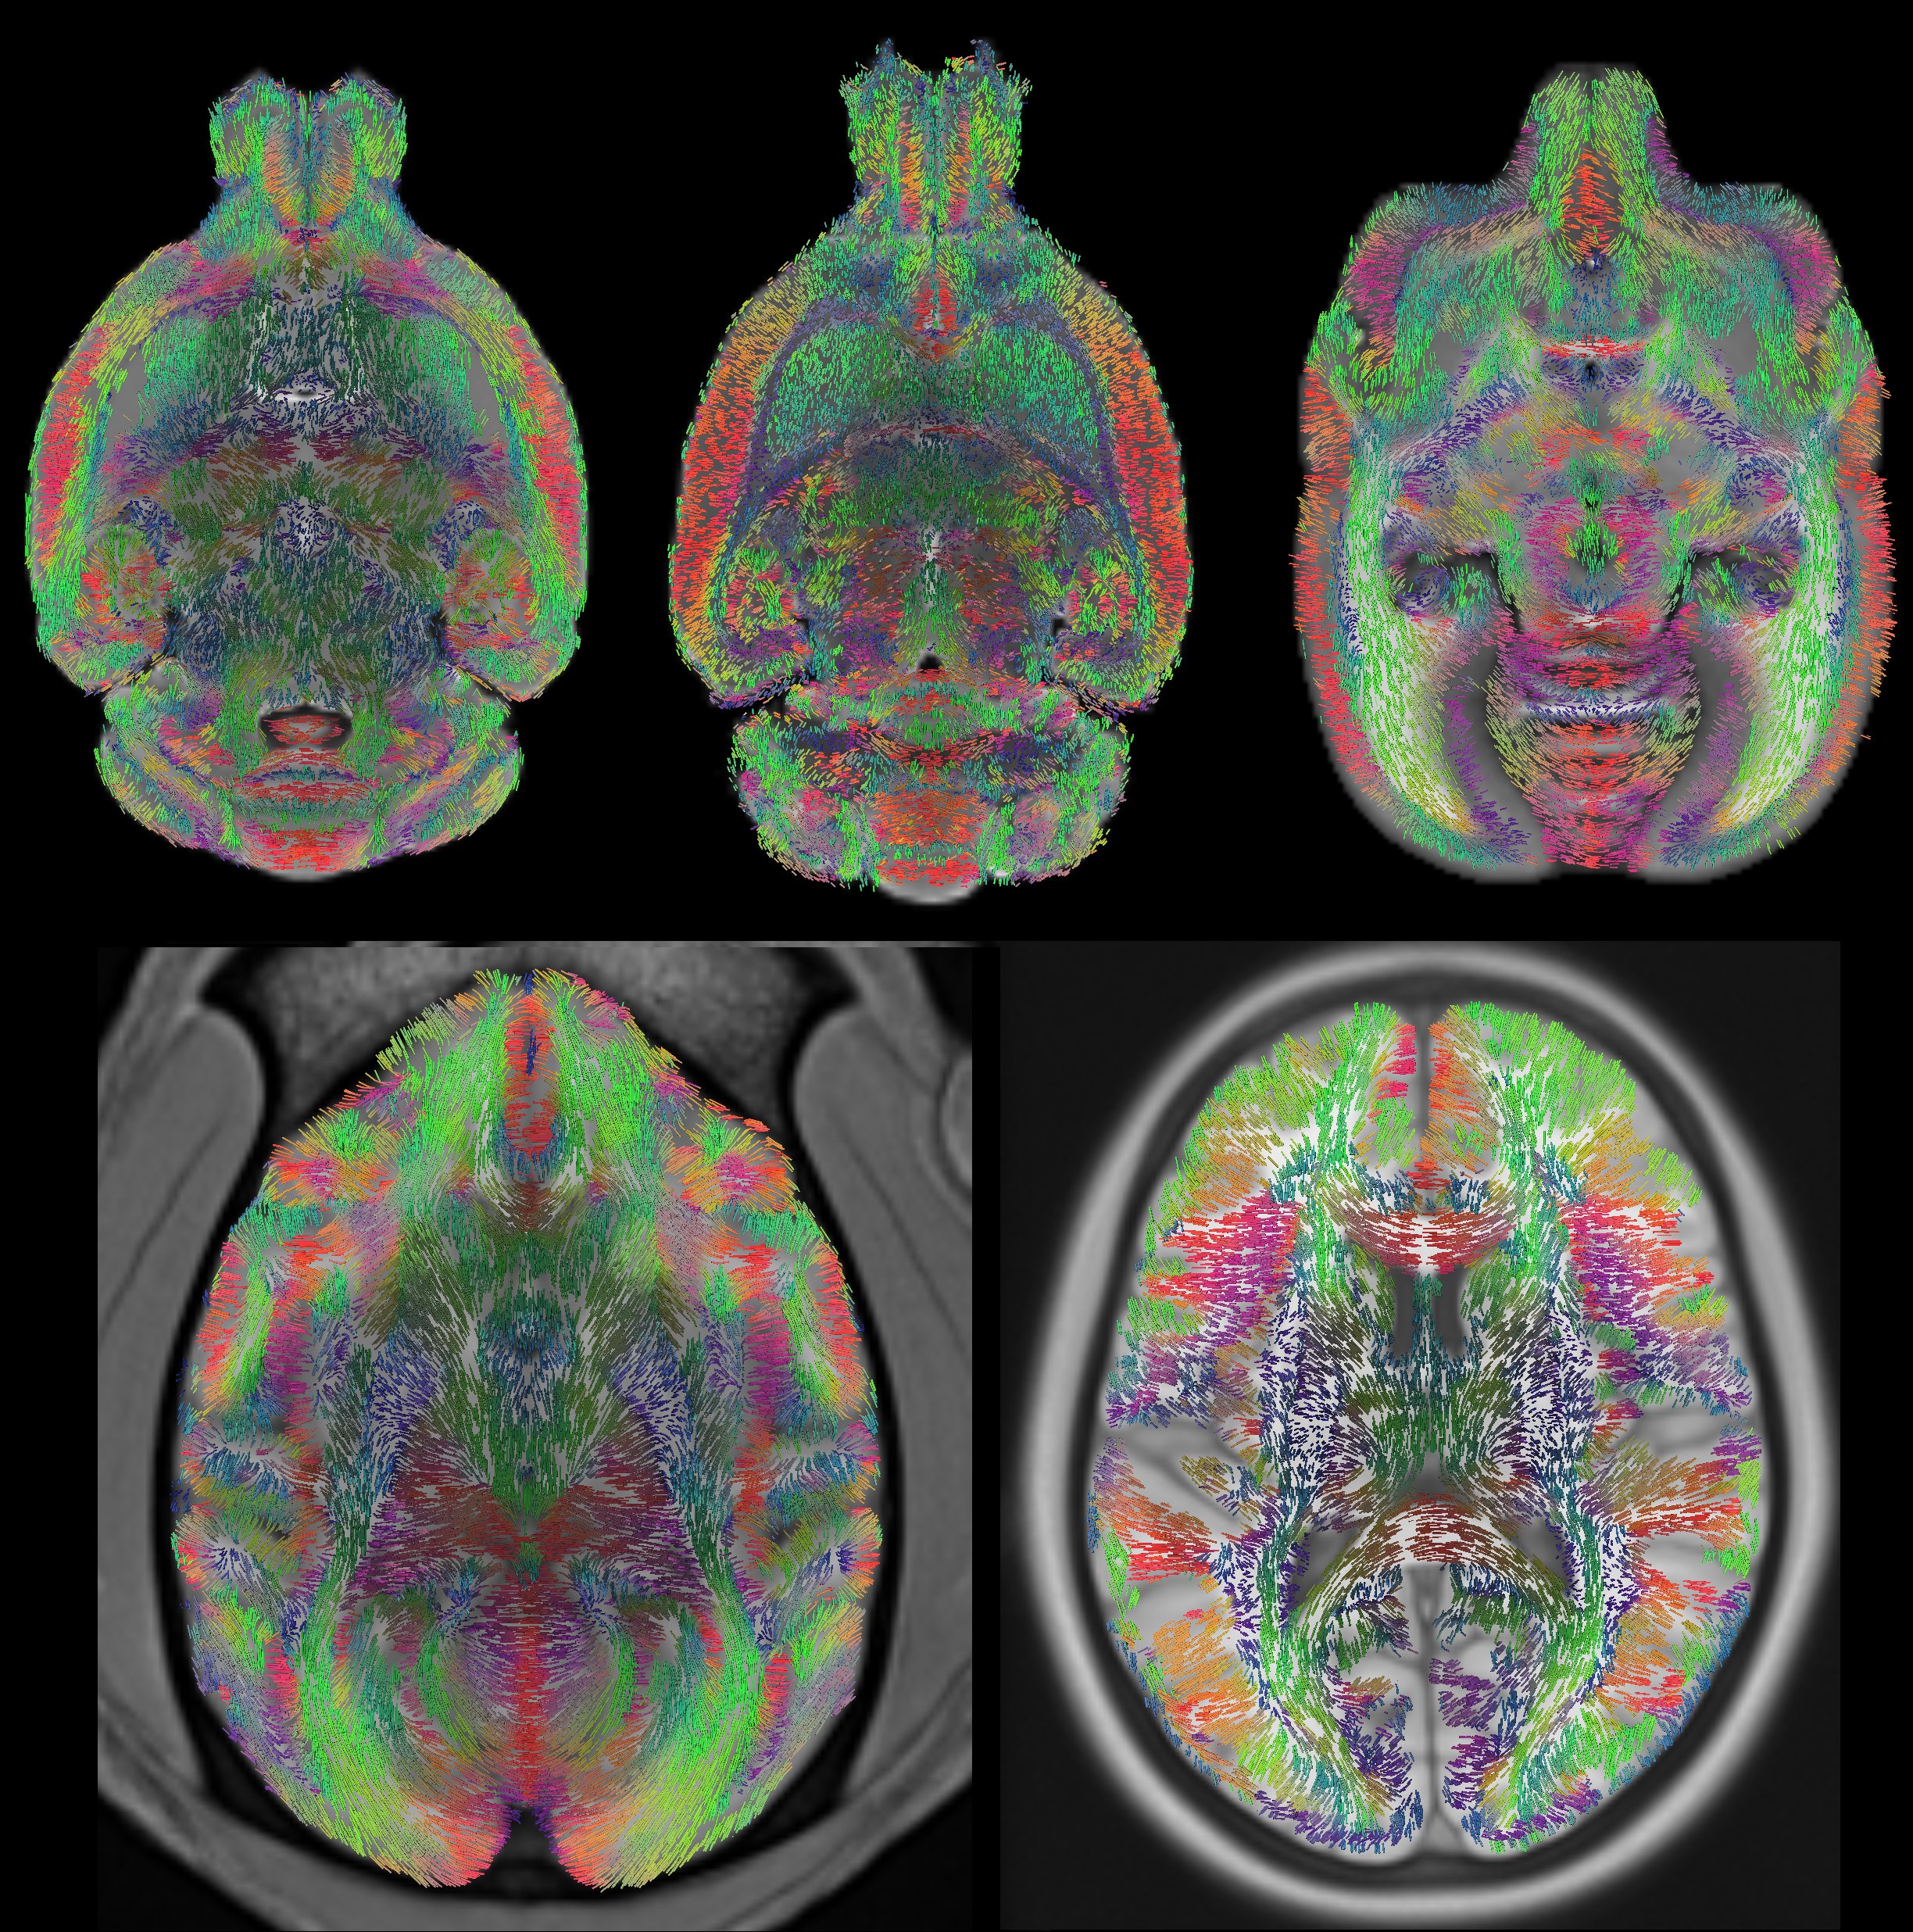

イメージング研究の範囲と高度化が進む中、高い評価を得ている「Imaging Neurons」の新版: MRI 顕微鏡、初期発生イベントのイメージング、単一ニューロンのラベル付けなどのトピックについて、20 以上の新しい章を追加しているため、開発にも対応しています。FRET、FCS/ICS、FRAP、超解像顕微鏡、単一分子イメージング、量子ドットを用いたイメージング、遺伝子発現のイメージングに関する章も含まれている。また、40以上の全章に加え、イメージング技術のプロトコルを40以上のセクションで紹介しています。商品の情報